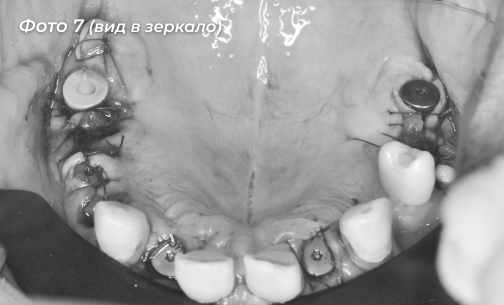

Было установлено 5 имплантов на верхней челюсти, 6-ой имплант был установлен ранее  (Фото 7, 8). Сразу дать нагрузку на импланты не решились в связи с тем, что костная ткань у пациента была рыхлая.